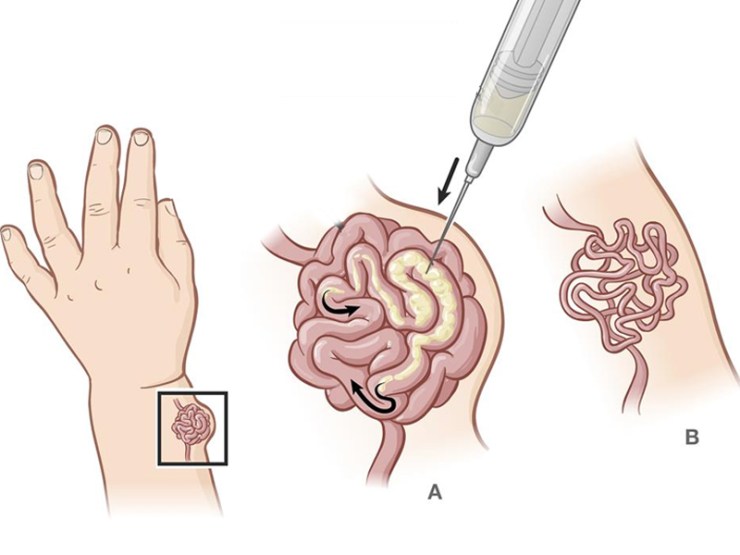

Absolute ethanol embolization is the only effective solution to destroy nidus.

Absolute ethanol if injected into nidus directly it will destroy inner lining cells of the nidus and nidus will resolve by it.

Why do you need experienced interventional radiologist to treat with absolute ethanol embolization?

Absolute ethanol goes into systemic circulation and it will destroy normal vessels also. And also leads to other fatal complications. So one has to go to centre where they are treating such cases with absolute ethanol and enough experience of it. Bankers Vascular Centre is one of the pioneer in India to start absolute ethanol embolization technique & has lot of experience to treat with absolute ethanol embolization.